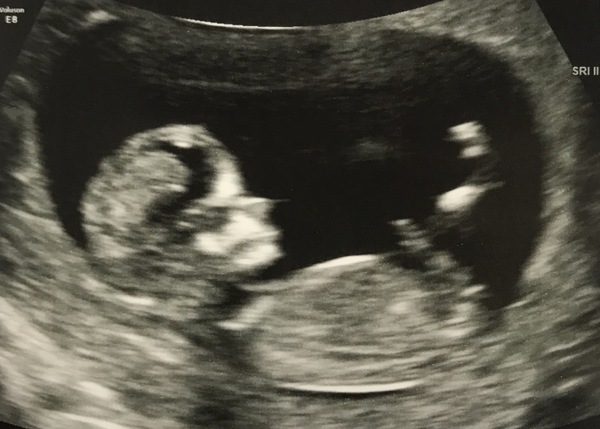

Had our scan yesterday and all is well! 12 weeks + 4 days so we have a due date of 13 August 2020 👶🏻❤️

Here is the little one 🥰

Good luck to everyone who has their scans soon I’m sure they will all go amazingly!

@missstripeypants that is such a clear beautiful scan, how exciting. My 12 week scan is next Wednesday, I cant wait but nervous at the same time. Only symptom I have is tiredness, still cant sleep through a whole night. Completely different to my first pregnancy so I think it's going to be a boy, I have a nearly 7 year old girl at the moment. Who keeps hugging my belly saying hows our little nic nak in there. Lol her nick name was tic tac.

Congratulations @MissStripeyPants such a lovely scan! Baby is looking great :) x

@MissStripeyPants Oh how wonderful and what a gorgeous clear photo that is. You must be super excited now it's all very real indeed!